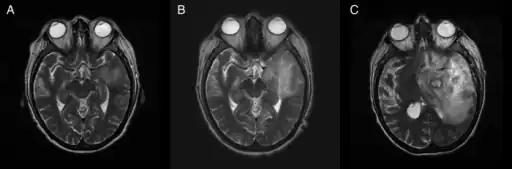

Image of granulomatous amoebic encephalitis caused by Acanthamoeba -

A: T2-weighted MRI showing liquefied, necrotic brain tissue as a result of GAE caused by Balamuthia mandrillaris

B: T1-weighted MRI showing expansion and addition of necrotic areas 4 days later